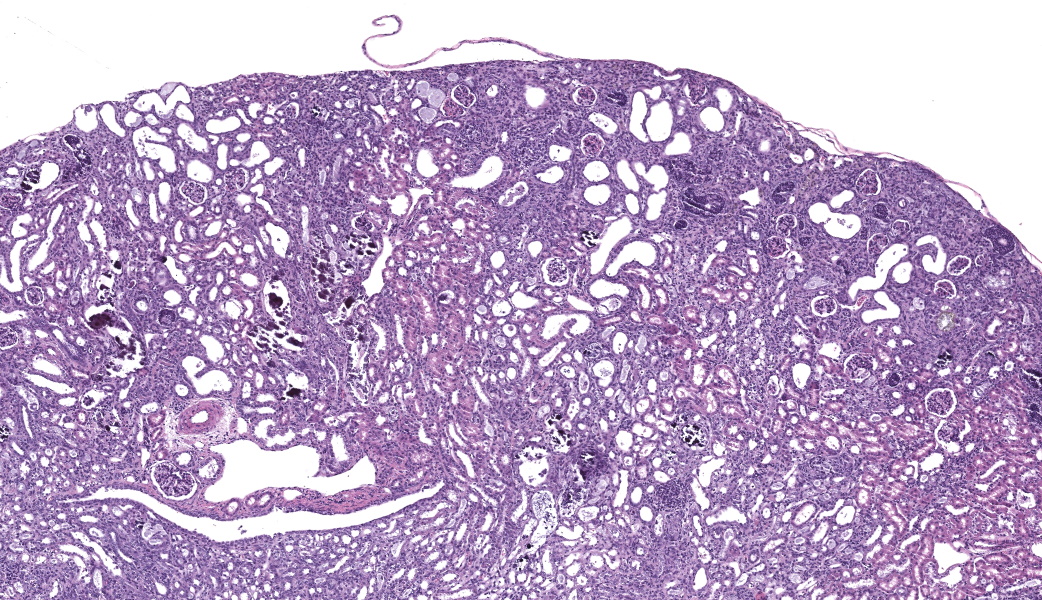

Kidney. The surface of the renal cortex is undulating with an irregular, scalloped appearance. Multifocally, renal tubules are dilated and have an attenuated epithelium. Dilated tubules are variably filled with an amorphous, pale basophilic material or abundant degenerate neutrophils, and less commonly contain brown to pale basophilic, spiculated, radiating birefringent crystalline material (2,8-dihydroxyadenine crystals) or dark basophilic coarsely granular material. Occasionally, crystal-filled tubules are surrounded by neutrophils, macrophages, and multinucleated giant cells. Often, Bowman’s spaces are mild to moderately dilated. Throughout the renal parenchyma, between tubules are streams of fibroblasts and collagen.

Rodents consuming a high-adenine diet begin to demonstrate evidence of renal injury, including reduction in creatinine clearance and intraluminal crystals, starting on day 3 after diet initiation.10 DHA crystals are brown, spiculated spheres which are birefringent in polarized light microscopy. Kidney lesions progresses as the diet is maintained, with tubular damage as the primary lesion. Crystals are primarily localized to proximal tubules and ascending limbs of the loops of Henle.10 Glomeruli are not directly injured by DHA nephropathy; however, dilation of the Bowman’s space is reported as a histologic finding of the adenine diet model.9 Direct tubular injury is accompanied by inflammation characterized primarily by macrophages which accumulate around injured tubules.10,15 Over time, tubular injury and inflammation progresses to interstitial fibrosis.

Kidney, cortex: Tubular degeneration, necrosis, and regeneration, chronic, diffuse, marked, with intratubular and interstitial crystals, granular and hyaline casts, mineralization, and interstitial fibrosis.